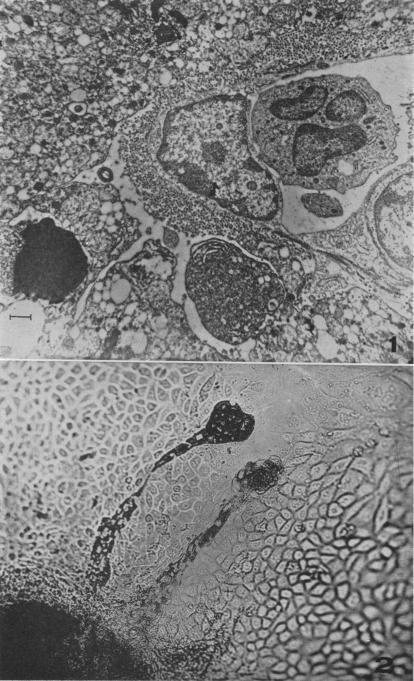

MOUSE MACROPHAGES AS HOST CELLS FOR THE MOUSE HEPATITIS VIRUS AND THE GENETIC BASIS OF THEIR SUSCEPTIBILITY.

Proc Natl Acad Sci U S A. 1960 Aug;46(8):1065-75. doi: 10.1073/pnas.46.8.1065.